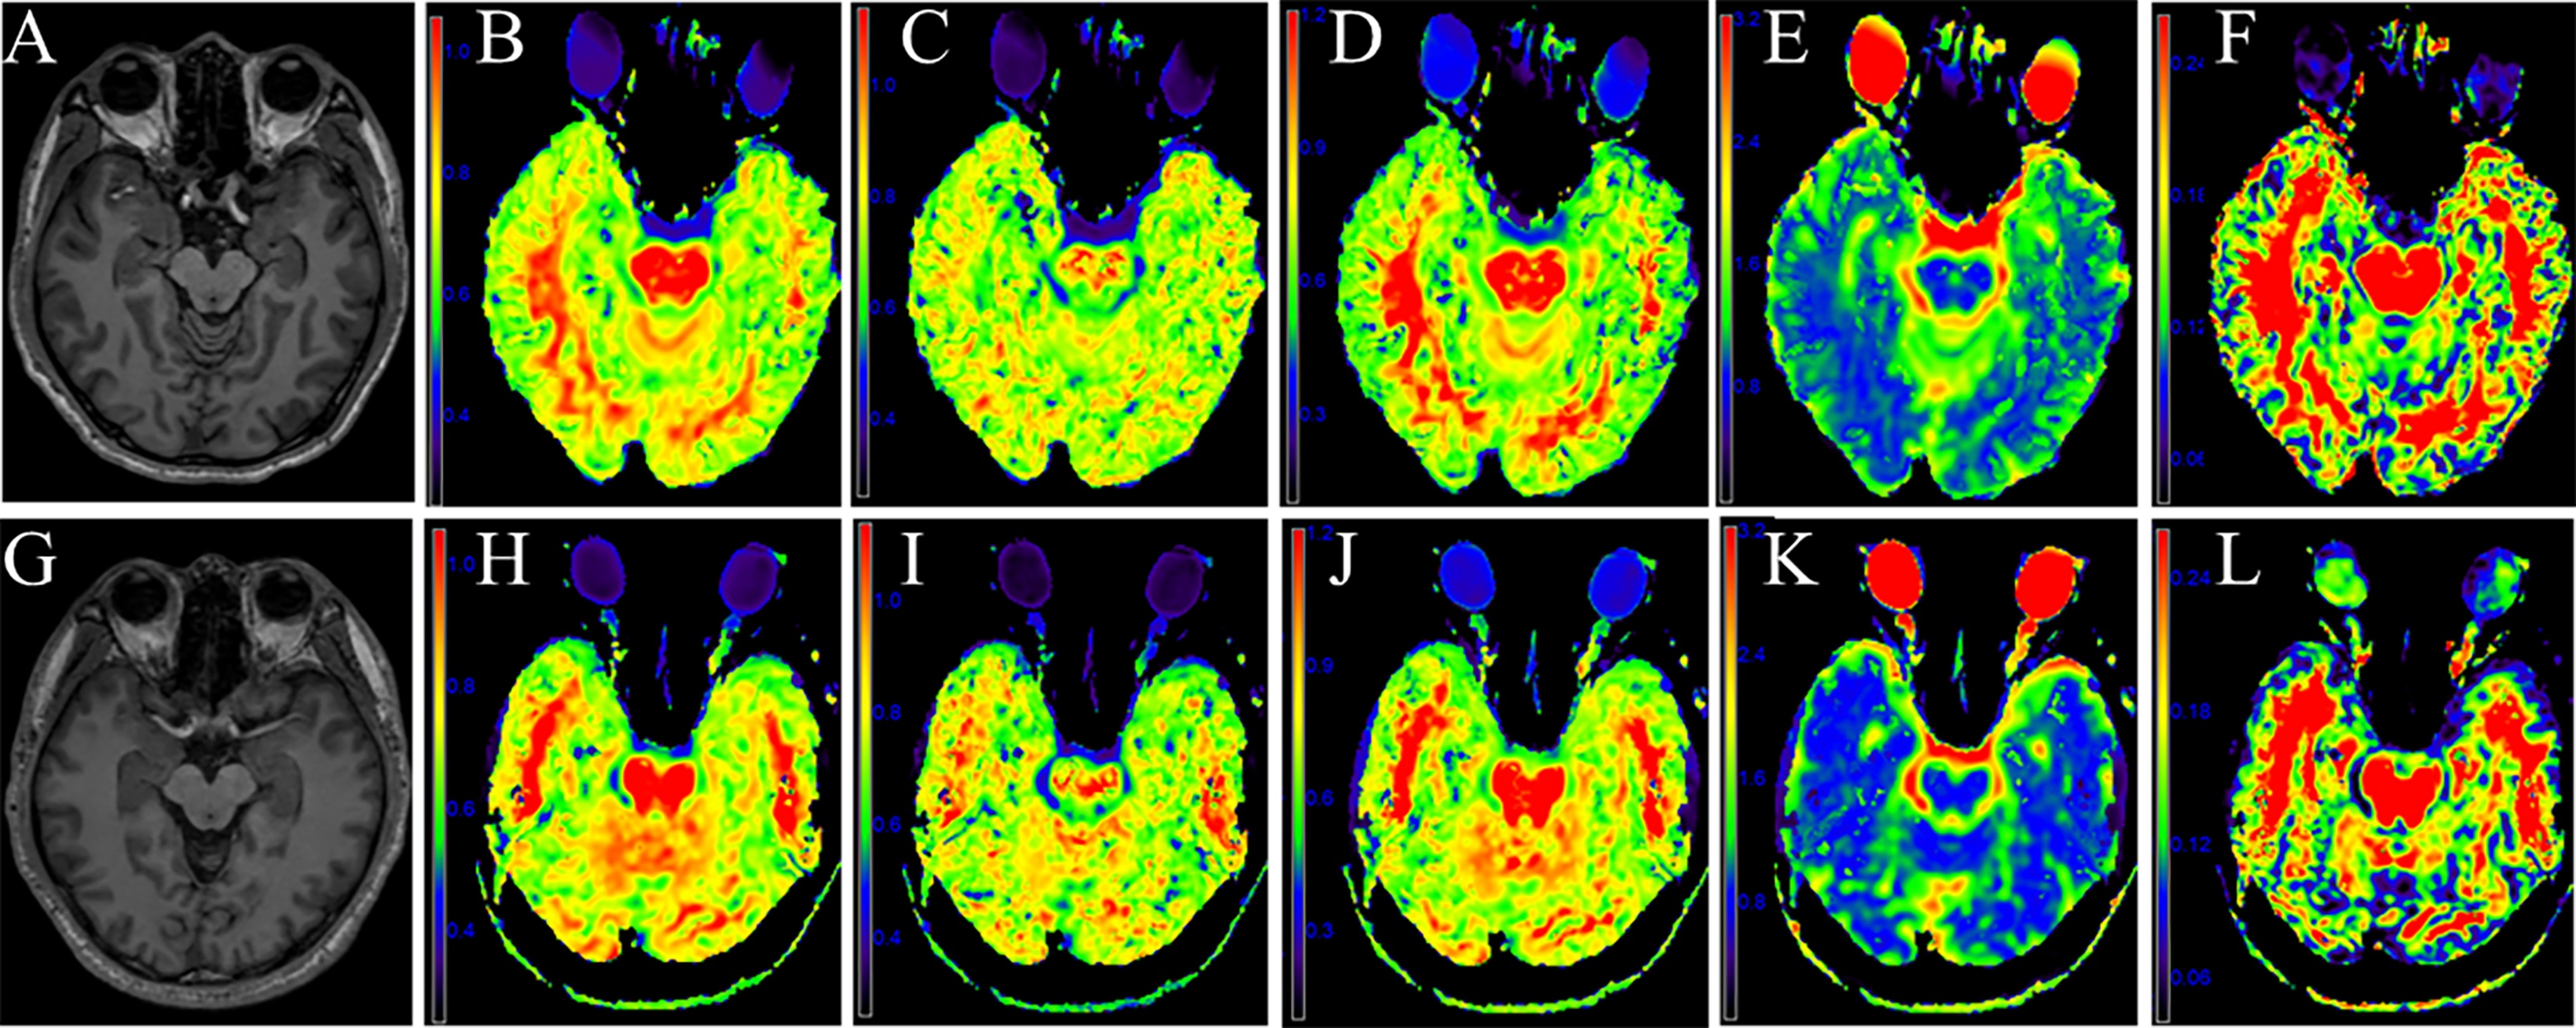

Fig. 2 A-F: A 46-year-old man with MCI. The volume in the right hippocampus shows slight atrophy on 3D-*) with decreased on MK (B), Ka (C), Kr (D) and FA (F) maps, increased on MD (E) maps. G-L:A 49-year-old man with NC. The volume in the right hippocampus shows slight atrophy on 3D-T1WI (G) with increased on MK (H), Ka (I), Kr (J) and FA (L) maps, decreased on MD (K) maps.